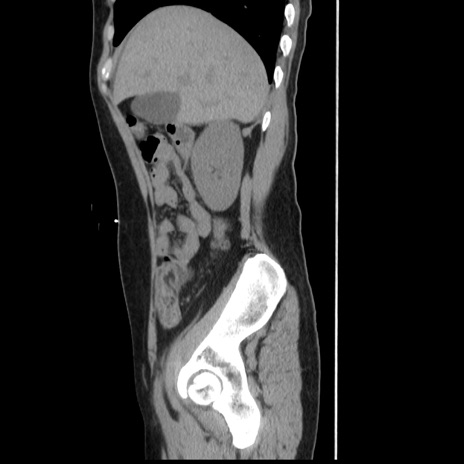

冠状断像

【症例】 50歳代女性

【主訴】 腹痛

【現病歴】前日生レバーを食べた。今朝に排便あり。 昼前に突然発症の腹痛を生じ、当院救急外来を受診した。

【既往歴】 子宮筋腫にてで子宮全摘後

【身体所見】 意識清明、腹部:平坦、軟、下腹部やや左を中心に圧痛・反跳痛あり、筋性防御あり

【データ】WBC 7800、CRP 0.07